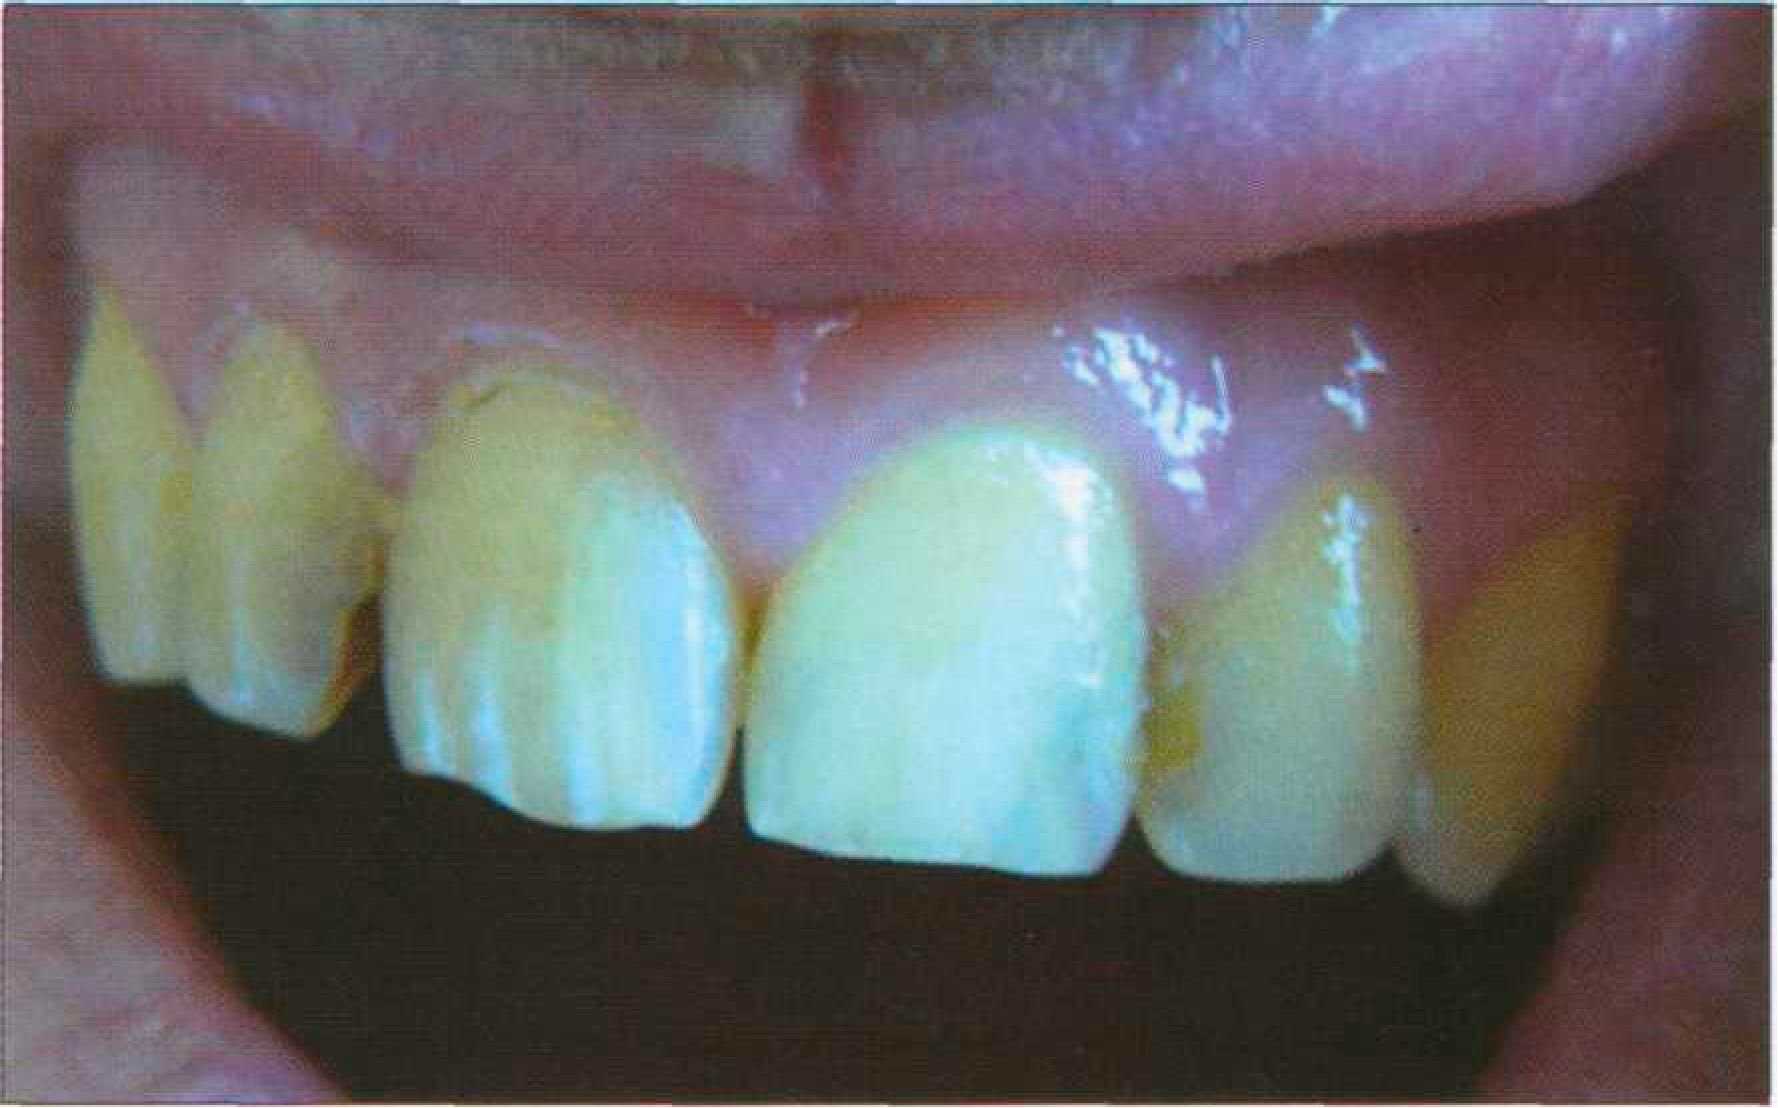

СИСТЕМНОЕ НАРУШЕНИЕ ОКРАСКИ ЗУБОВ Очаговая деминерализация эмали в виде системного поражения пришеечных участков зубов как разновидность приобретенной гипоплазии или гипокальцификации, формируется в период созревания тканей после прорезывания. В отличие от начального кариеса поражаются не отдельные, а практически все зубы. Клинически определяются меловидно измененные участки, особенно контрастные при высушивании струей воздуха (рис. 172).

Экзогенное системное нарушение окраски эмали (дентина) может быть связано с действием неблагоприятных производственных и экологических факторов. Начальные этапы кислотного некроза эмали клинически и морфологически мало отличаются от начального кариеса. Множественные меловидные пятна локализуются на вестибулярной поверхности преимущественно фронтальных зубов, занимая площадь от режущего края до придесневой области. |